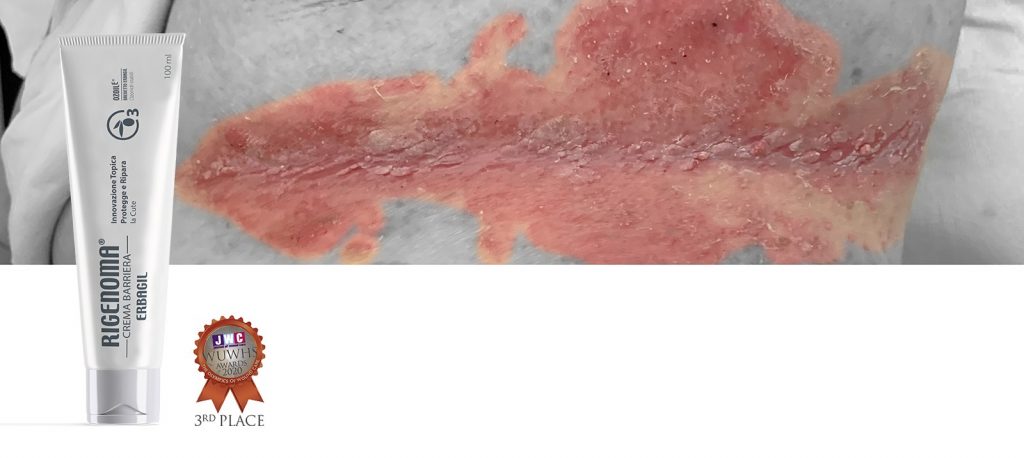

RIGENOMA CREMA BARIERĂ

Pansament primar bioactiv sub formă de cremă barieră cu efect de ecranare non-ocluziv cu Ozoile® și Cera Alba Crema este indicata in prevenire si tratamentul leziunilor cutanate de la incontinență urinara, chiar cu colonizare bacteriană suprapusă (impetigo) și/sau infectii fungice si in prevenirea escarelor de decubit. Utilizarea sa este indicata în caz de dermatită asociată cu incontinență urinara, eritem cu maceratie localizat în diferite zone ale corpului (sant submamar, axile, inghinal etc.), leziuni de eczema si impetigo

Protejează de traumatismele de lipire și de frecare, permite o schimbare atraumatică și nedureroasă și aderența altor pansamente.

Descriere

Ozoile®, un complex patentat de molecule obținut dintr-un proces tehnologic ecologic în care Ozonul se leagă de legăturile olefinice duble ale uleiului organic de măsline, datorită naturii sale uleioase, creează un film lipidic protector care hidratează, lubrifiază și protejează. Ozoile® inhibă COX2 și contracarează procesele degenerative oxidative prin acțiunea de eliminare.

RIGENOMA CREMA BARIERĂ

Pansament primar bioactiv sub formă de cremă barieră cu efect de ecranare non-ocluziv cu Ozoile® și Cera Alba Crema este indicata in prevenire si tratamentul leziunilor cutanate de la incontinență urinara, chiar cu colonizare bacteriană suprapusă (impetigo) și/sau infectii fungice si in prevenirea escarelor de decubit. Utilizarea sa este indicata în caz de dermatită asociată cu incontinență urinara, eritem cu maceratie localizat în diferite zone ale corpului (sant submamar, axile, inghinal etc.), leziuni de eczema si impetigo

Protejează de traumatismele de lipire și de frecare, permite o schimbare atraumatică și nedureroasă și aderența altor pansamente.